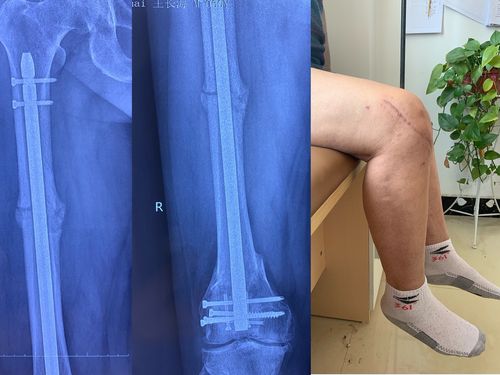

术后3个月骨痂形成及功能照!

请问我的髌骨骨折长骨痂了吗?

髌骨骨折骨痂形成图片

髌骨骨折长骨痂图

骨折后骨痂形成图片

骨折骨痂形成图片对比

骨折术后100天骨痂图